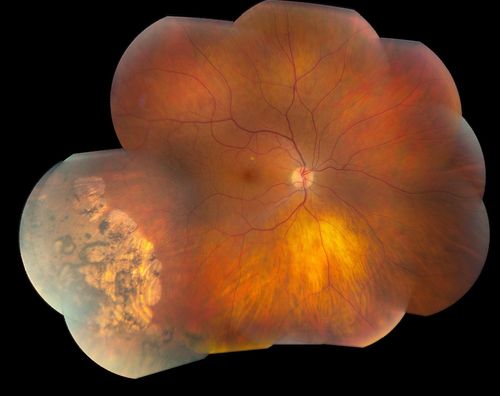

Pigmented Peripheral Retinal Degeneration

42-year old male comes in for routine eye exam and to follow up on peripheral retinal degeneration in both eyes. VA is 20/20, right eye and 20/25, left eye. Patient is asymptomatic with no visual complaints.

Mayo Clinic Jacksonville, Florida

TOPCON TRC 50-EX